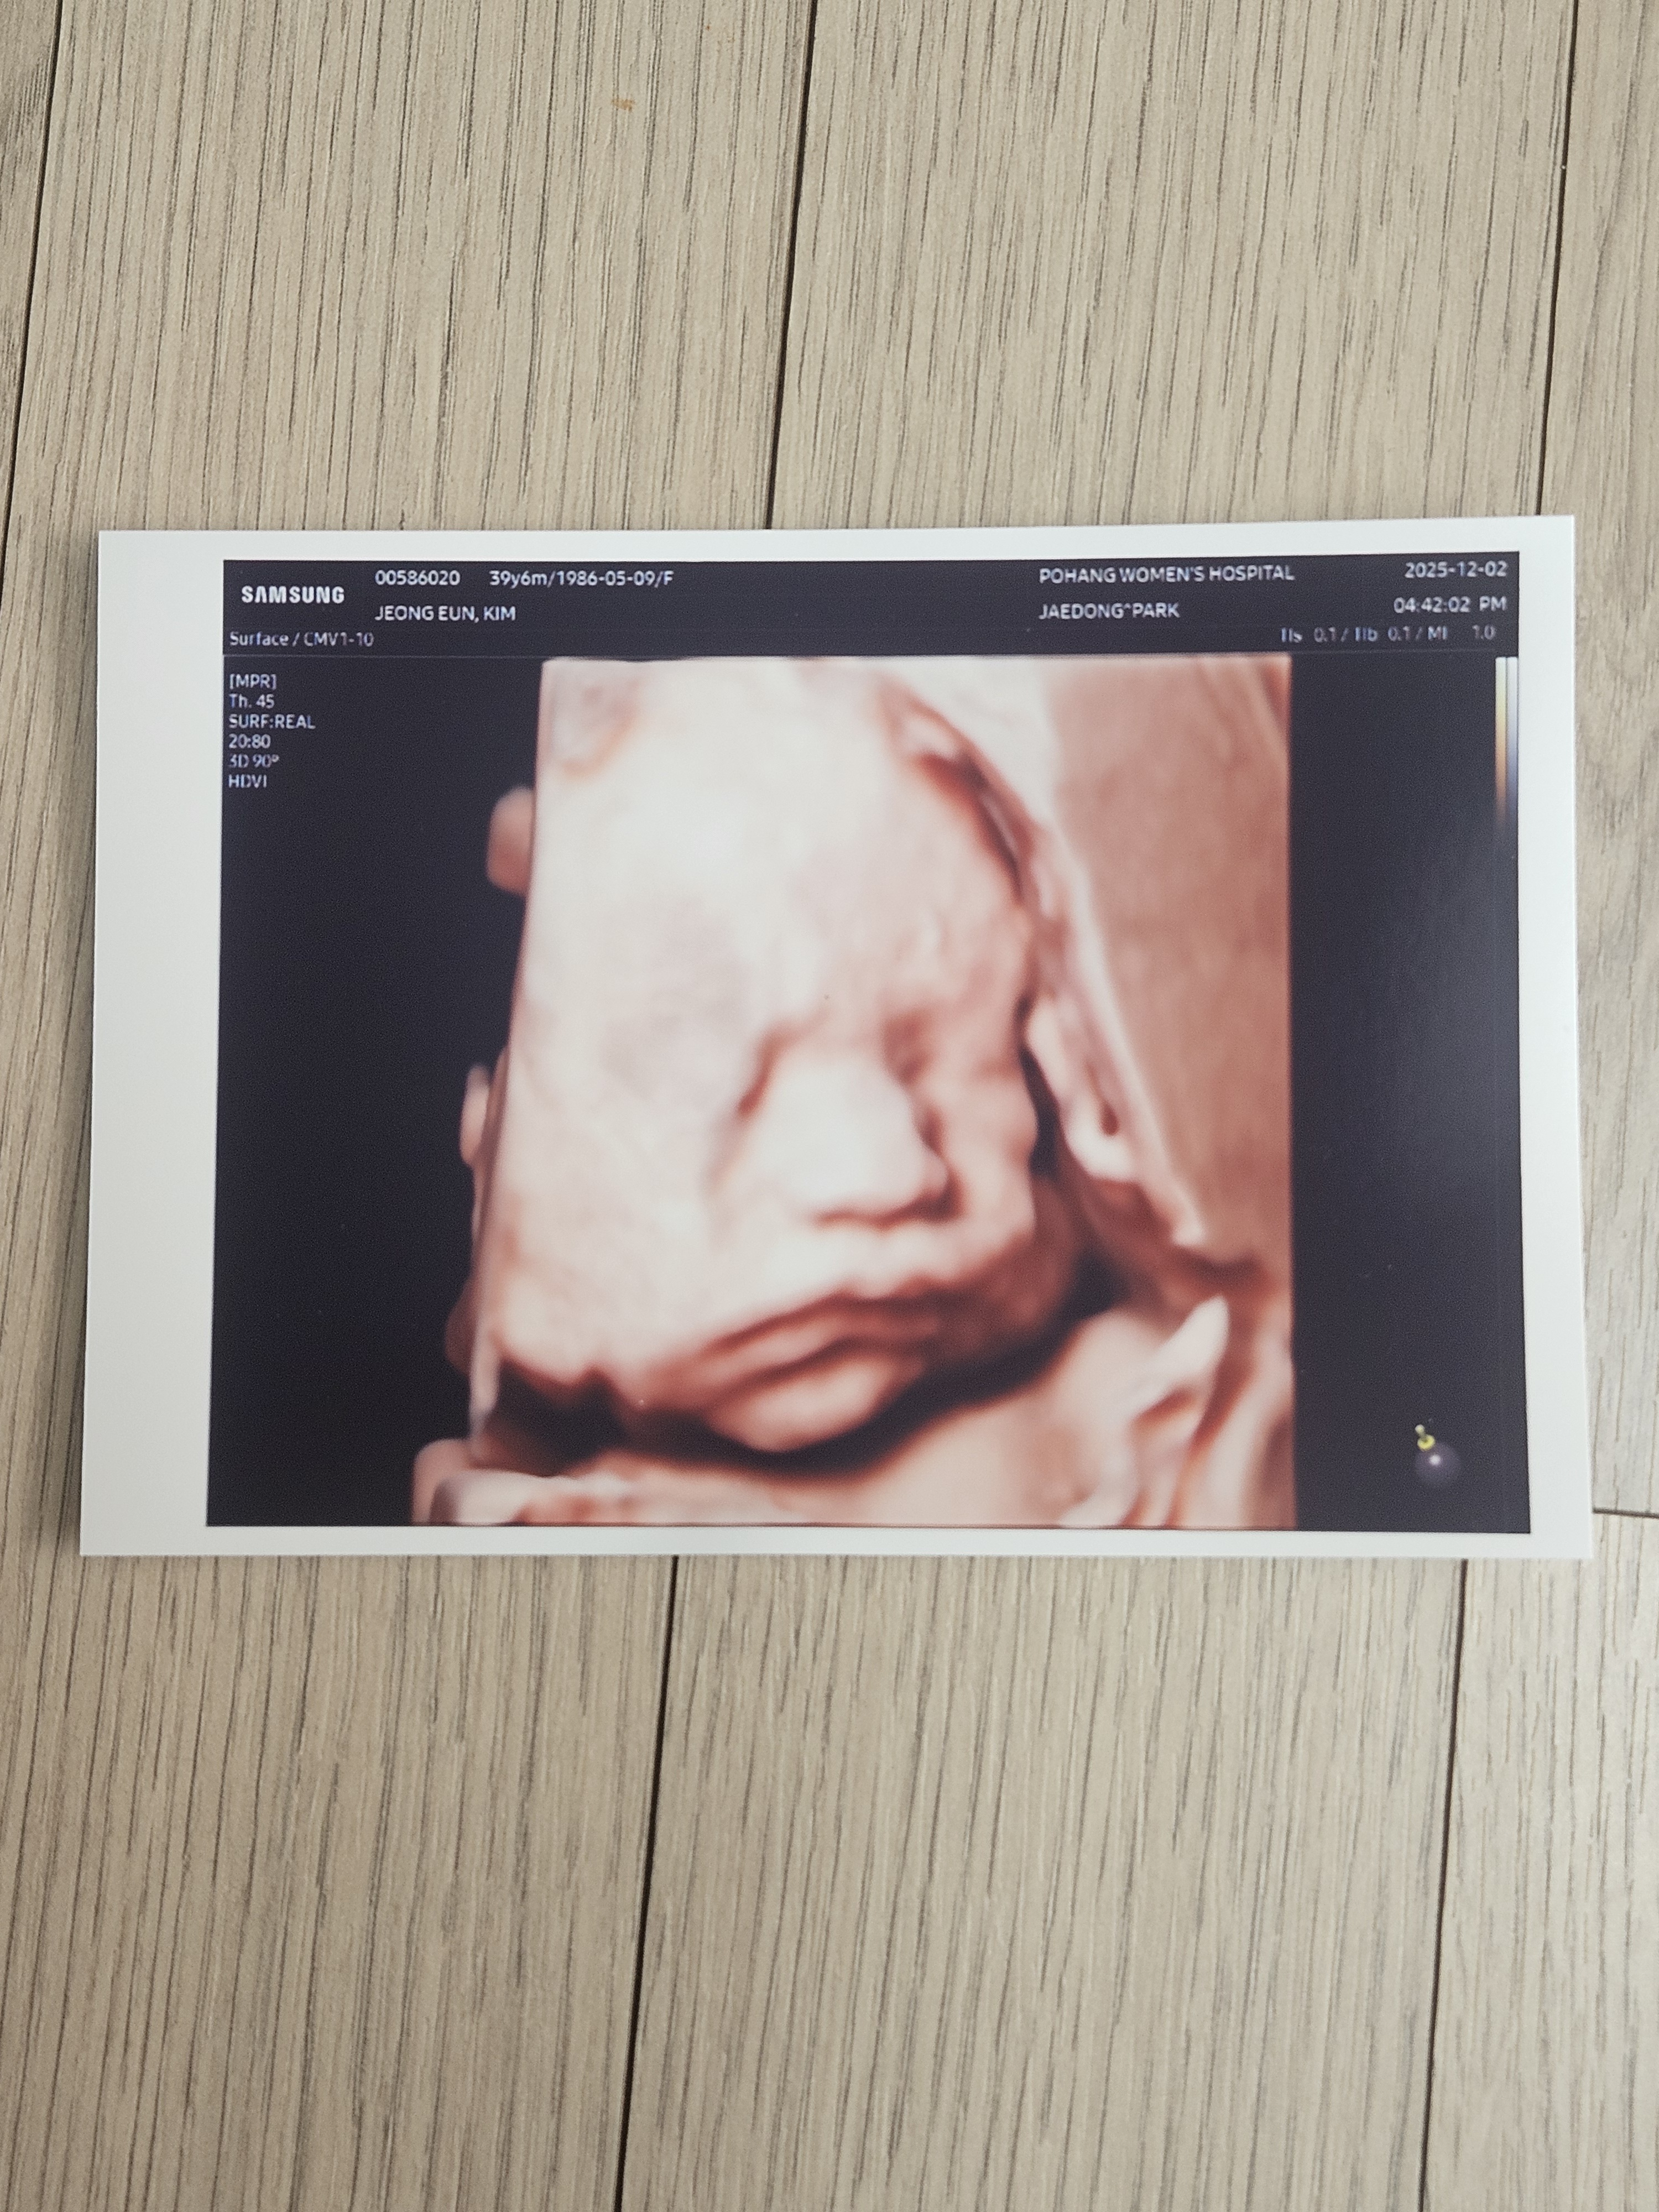

초음파 사진 접수완료

김정은님의 사연 · 2025.12.03

아기 성별

👶🏻 남아

"또아야 꼬물이 시절 아주 작디작았는데 열심히 잘 성장해서 만날날이 다가오니 엄마는 너무 기쁘고 좋구나😍 제일 귀여웠던 곰젤리 모습 본지도 엊그제 같은데 너무 잘자라줘서 벌써 몸무게 1kg대에 진입했다니 놀랍고 기뻐^-^ 태어날때까지 엄마 품속에서 잘 지내다가 내년 2월에 세상에 뿅하고🌟🎉건강하게,예쁘게 태어나자!! ㅋ 태어나면 응애 응애 하고 우렁차게 울어줄 울또아 기대되고 기다려져🫶 엄빠에게 와주고 ,건강히 잘 자라줘서 너무너무 고"